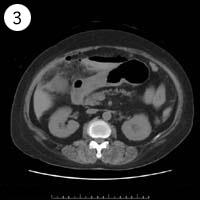

57歳 女性

異常のある4枚組は?

単純CT